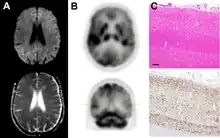

Brain FDG PET-CT tends to be markedly abnormal, and is increasingly used in the investigation of dementias.

- Patients with CJD will normally have hypometabolism on FDG PET.[52]

Testing of tissue remains the most definitive way of confirming the diagnosis of CJD, although it must be recognized that even biopsy is not always conclusive.[53]

In one-third of people with sporadic CJD, deposits of "prion protein (scrapie)", PrPSc, can be found in the skeletal muscle and/or the spleen.[54] Diagnosis of vCJD can be supported by biopsy of the tonsils, which harbor significant amounts of PrPSc; however, biopsy of brain tissue is the definitive diagnostic test for all other forms of prion disease. Due to its invasiveness, biopsy will not be done if clinical suspicion is sufficiently high or low. A negative biopsy does not rule out CJD, since it may predominate in a specific part of the brain.[55]

The classic histologic appearance is spongiform change in the gray matter: the presence of many round vacuoles from one to 50 micrometers in the neuropil, in all six cortical layers in the cerebral cortex or with diffuse involvement of the cerebellar molecular layer.[56] These vacuoles appear glassy or eosinophilic and may coalesce. Neuronal loss and gliosis are also seen.[57] Plaques of amyloid-like material can be seen in the neocortex in some cases of CJD.[58]

- ↑ Morley NC, Hofer M, Wilkinson P, Bradley KM (2021). "18FDG PET-CT in sporadic Creutzfeldt–Jakob disease, correlated with MRI and histology". World J Nucl Med. 20 (4): 411–413. doi:10.4103/wjnm.wjnm_5_21. PMC 8686746. PMID 35018165. S2CID 244465297.